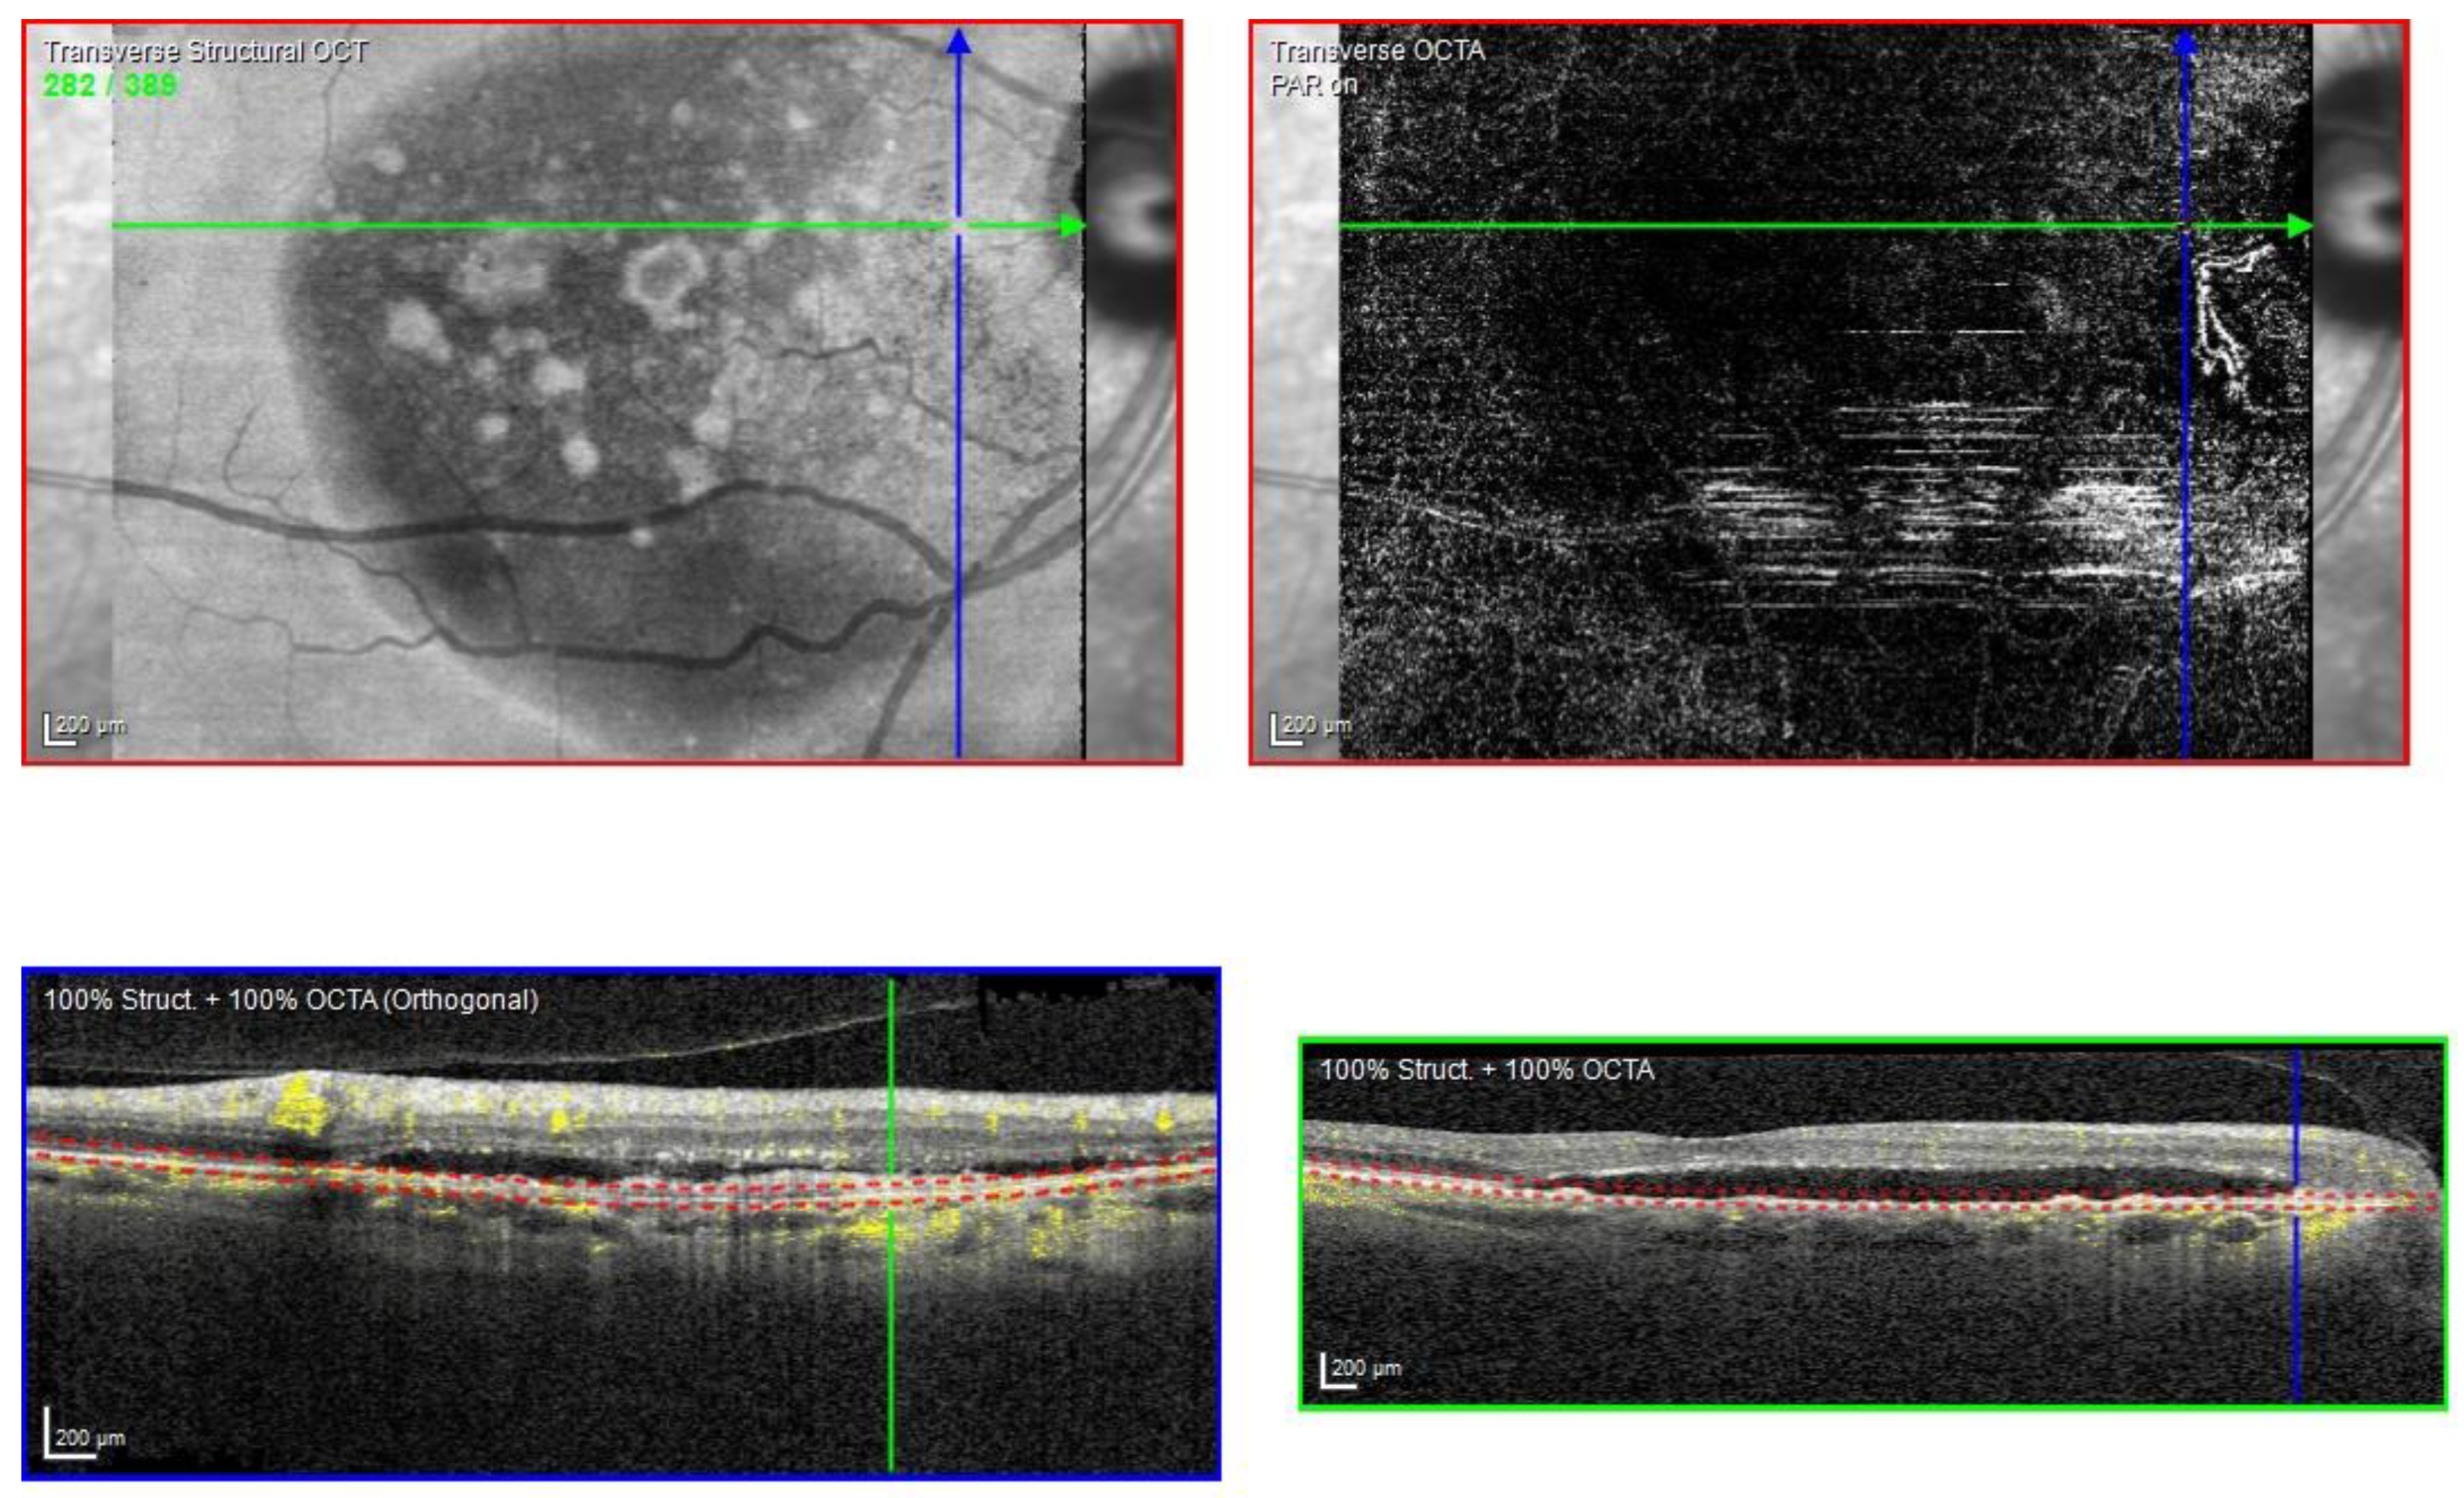

Figure 2.

Case 1. Heidelberg Spectralis optical coherence tomography angiography shows a subretinal neovascular membrane in the left eye.

The optical coherence tomography angiography (OCTA) scan confirmed the presence of MNV in the left eye (Figure 2). Based on clinical findings and multimodal imaging, the patient was diagnosed with left nAMD. Anti-vascular endothelial growth factor (VEGF) intravitreal injections were commenced, according to a treat and extend (T&E) regimen. To date, the patient received four intravitreal injections. Since the first injection, the OCT scan showed a complete resolution of the BALAD (Figure 1D). However, a retinal pigment epithelium (RPE) tear was noted (Figure 1E). The BCVA did not improve (1.5 logMAR on the last examination).

The OCTA scan confirmed the presence of MNV (Figure 7A,B).

Figure 7.

Case 5. Heidelberg Spectralis optical coherence tomography angiography shows a subretinal neovascular membrane in right (A) and left eyes (B).